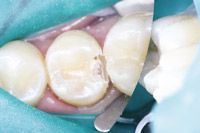

A thin layer of TheraCal LC was placed on the dentin over the deepest portions of the preparation using the convenient syringe delivery system and then light cured for 20 seconds (Fig. 4).

Fig. 4